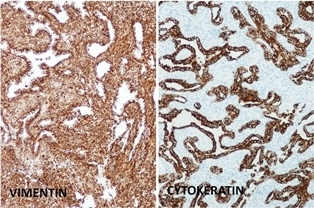

Synovial sarcoma is a common soft tissue malignancy accounting for 5 – 10 % of soft tissue sarcomas. Patients with synovial cell sarcoma are often between the ages of 15 and 35 years old; generally younger than patients with other types of soft tissue sarcomas. The most probable cellular origin is an undifferentiated mesenchymal cell. The tumor may be monophasic or biphasic meaning having one or two different types of cells that make up the tumor. The monophasic type is frequently composed of relatively uniform malignant appearing spindle cells with a fascicular arrangement. The biphasic type is similar to the monophasic but with epithelial clusters or glandular-like spaces. Synovial sarcoma has a fusion gene, SYT-SSX, which is the result of a chromosomal translocation unique for this tumor, t(x;18)(p11;q11), which is present in up to 90% of cases. Synovial sarcoma whether monophasic or biphasic stains positive for vimentin and epithelial makers such as cytokeratin and epithelial membrane antigen (EMA)

Biphasic form is composed of both epithelial-cell and spindle-cell components in equal proportions (Fig. 6-8)

Inmunohistochemical profile: Vimentin (+), Cytokeratin (+), Epithelial Membrane Antigen EMA (+)